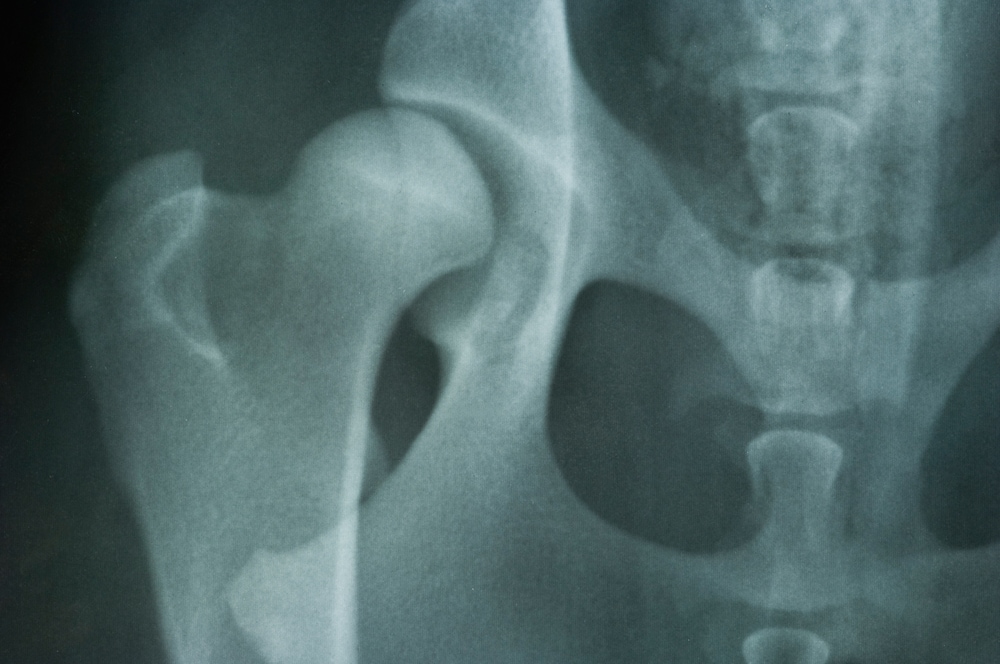

Hip dysplasia in Dogs is a disease of the hip in which the ball and socket joint is malformed. This malformation means that the ball portion and its socket don’t properly meet one another, resulting in a joint that rubs and grinds instead of sliding smoothly.

The hip joint is composed of the ball and the socket. The development of hip dysplasia is determined by an interaction of genetic and environmental factors, though there is a complicated pattern of inheritance for this disorder, with multiple genes involved. Hip dysplasia is the failure of the hip joints to develop normally (known as malformation), gradually deteriorating and leading to loss of function of the hip joints.

X-rays are crucial for visualizing the signs of hip dysplasia. Some of the possible findings may be degenerative disease of the spinal cord, lumbar vertebral instability,bilateral stifle disease and other bone diseases.

Your veterinarian will schedule follow-up appointments with you to monitor any changes in your dog's hip dysplasia. X-rays will be taken for comparison with previous x-rays. If your dog has undergone surgery, these x-rays will indicate the rate of post-surgical healing. If your dog is being treated as an outpatient only, the x-rays may indicate the rate of deterioration in the hip joint.